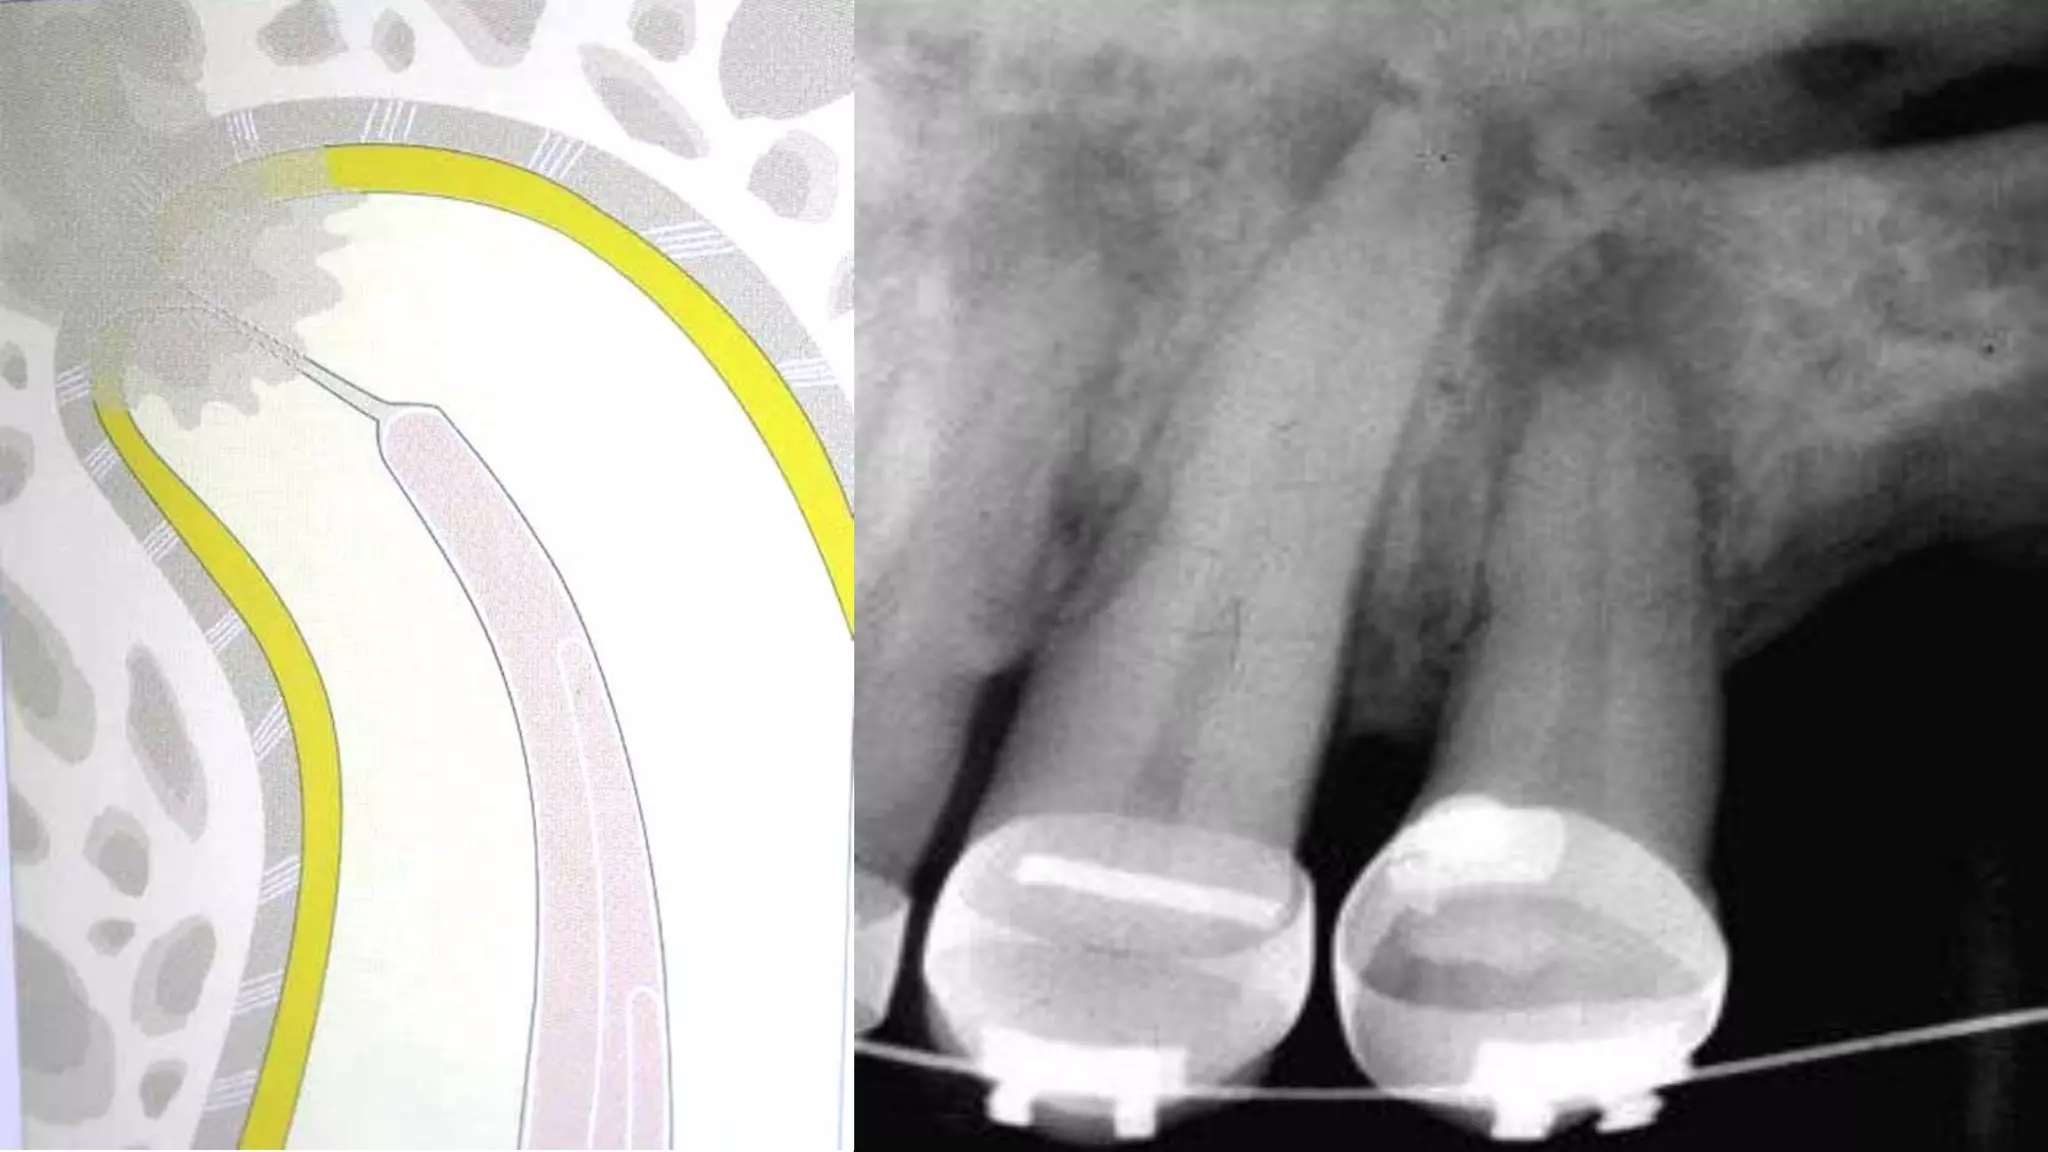

BLUNDERBUSS APEX

newly erupted tooth showing an

incompletely formed root having a

wide canal and the pulp may get

necrosed due to caries or trauma

and may require root canal

standard instrumentation and

obturation techniques are not

favorable

Open Apex

Endodontic management of the pulpless,

permanent teeth with wide open blunder buss

apex offers dentists a most difficult condition

to treat.

Problem of open apex - the open apex occurs

when trauma or caries cause pulpal exposure

prior to the completion of root development.

An open apex refer to absence of sufficient root

development to provide a conical taper to the

canal - “Blunderbuss” canal.

Since it is necessary to seal the apex to gain

endodontic success, it is physically impossible to

achieve this objective through ordinary procedure

in open apex cases. www.indiandentalacademy.com